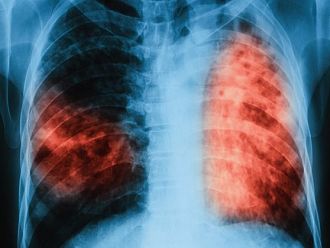

За пореден път през 2019 г. ще се проведат безплатни прегледи за туберкулоза в лечебни заведения за диагностика и лечение на туберкулозата в областните градове на страната. Кампанията „Седмица на отворените врати” се осъществява в изпълнение на Националната програма за превенция и контрол на туберкулозата в Република България. Чрез предоставянето на безплатен достъп до медицински услуги проявата е доказала своята ефективност за повишаване на обществената информираност по отношение на заболяването, съобщиха от Министерството на здравеопазването.

По време на проведени кампании през месеците март и юни 2019 г. общо анкетирани за туберкулоза са 5 057 лица, а на 3 293 лица в риск от туберкулоза са извършени медицински прегледи и допълнителни изследвания. Открити са 53 лица с туберкулоза и 144 лица с латентна туберкулозна инфекция, при които е започнато лечение.

Инициативата се провежда от 2009 г. и е допринесла за по-добра разкриваемост на случаите на туберкулоза и латентна туберкулозна инфекция, за ефективна превенция на туберкулозата в страната и за подобряване на достъпа до здравни грижи. По време на проведените за периода 2009 г. – 2018 г. „Седмици на отворени врати” анкетирани за туберкулоза са 119 787 лица, открити и насочени за лечение са 1 295 лица с туберкулоза, открити с латентна туберкулозна инфекция и обхванати с химиопрофилактика са 4 495 души.

По време на „Седмицата на отворените врати“ на всеки желаещ се предлага скрининг за риска от туберкулоза чрез анкета и консултации. На лицата, които са в риск, се провеждат допълнителни прегледи и изследвания. При откриването на случаи на туберкулоза своевременно се предприемат мерки за хоспитализация и лечение, в резултат на което се прекъсва веригата за предаване на инфекцията.